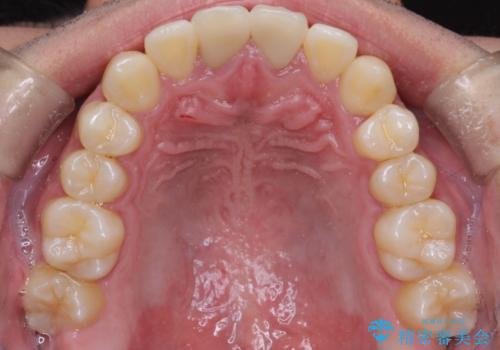

- 前歯のガタガタを主訴に来院されました。

上下の前歯のガタガタと左上の歯が反対にかんでいる状態でした。

上下の歯と歯の間をわずかに削り並べる計画としました。

目立たずに歯並びがよくなり、前歯に装着されたセラミックも壊さずに矯正治療が終了し満足していただけました。